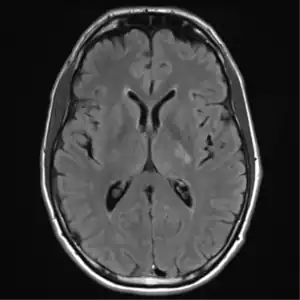

![]() ![]() text: From left to right: Cryptococcosis lung, cryptococcosis brain | |

MRI brain: cryptococcus